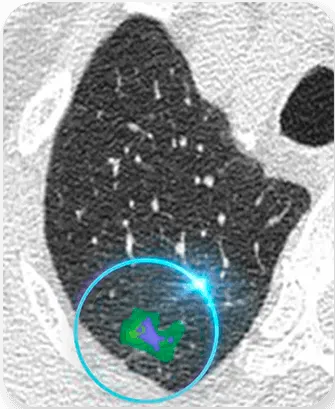

How low is Ultra-low radiation?

97% lower radiation than regular imaging machines.

Our Fujifilm devices powered with AI allow us to deliver precise and accurate results for early detection.

Ultra-Low-Dose Scan

Low-Dose

Scan

High-Dose Scan

High-Dose

AI Enhanced Ultra-Low-Dose Scan

AI Enhanced Ultra

Low-Dose Scan

Is the CT scan safe?

Yes, the CT scan at NURA is safe. The machines use ultra-low doses of radiation, which is 1/50th lower than regular imaging machines.

One of the key advantages of choosing Nura is the inclusion of AI technology. Many people book Nura’s full body scan test to detect lifestyle diseases and cancer risk in lungs, liver, kidneys, pancreas, and other vital organs.

Early detection saves lives. People searching for a full body scan test or a whole body scan near me want more than a routine evaluation. Nura’s AI-supported imaging can detect organ-level changes and risks long before symptoms appear. This makes the checkup not just preventive but also strategically life-saving.